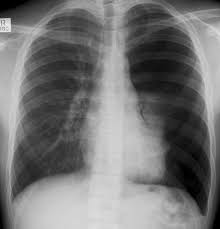

Hyperlucency x ray definition. The obstruction that leads to lobar emphysema typically causes dynamic hyperinflation which manifests radiographically as lobar hyperlucency and mediastinal shift on the chest x ray. Spirometery of the patient was within normal limits. Even in adults pulmonary hyperlucency can be caused by congenital and acquired conditions. Information and translations of lung hyperlucent in the most comprehensive dictionary definitions resource on the web.

Abstract pneumothorax is the most urgent cause of a hyperlucent thorax. The radiographic finding that a lung or portion thereof is less dense than normal as from air trapping by a bronchial foreign body asymmetric emphysema or decreasing blood flow. Emphysema causes both over inflation and decreased pulmonary vasculature. Asymmetrical distance between the medial.

An x ray simply is fundamentally useless to properly diagnose your problem. A rotated posterior anterior view may result in artifactual decreased attenuation on the side rotated anteriorly because of a shorter distance between the patient and the incident x ray beam. Hyperlucency imaging a region on a plain film with tissue density allowing for transmission of x rays. Initial interpretation should include excluding pseudo causes of hyperlucency because of technical factors.

Spirometery of the patient was within normal limits. The most common causes of pulmonary hyperlucency in adults are summarized in figure 1. Hyperlucent lungs result from air trapping or decreased pulmonary vasculature. Unilateral hyperlucent lung.

Contrast enhanced computed tomograph cect of the chest showed an unremarkable lung fields and vasculature. An understanding of the broad differential di agnosis of pulmonary hyperlucency is necessary to determine the underlying cause and provide appropriate patient care. Every unnecessary x ray in a woman of child bearing age represents a danger that should be weighed against the benefits. What does lung hyperlucent mean.